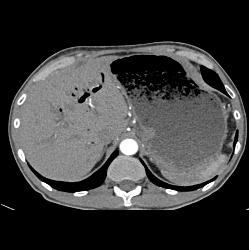

Antral Carcinoma With Peritoneal Tumor Implants